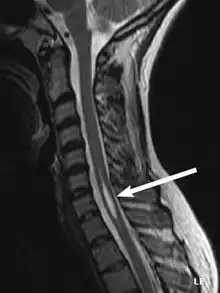

Physicians now use magnetic resonance imaging (MRI) to diagnose syringomyelia. The MRI radiographer takes images of body anatomy, such as the brain and spinal cord, in vivid detail. This test will show the syrinx in the spine or any other conditions, such as the presence of a tumor. MRI is safe, painless, and informative and has greatly improved the diagnosis of syringomyelia.[18]

The possible causes are trauma, tumors, and congenital defects. It is most usually observed in the part of the spinal cord corresponding to the neck area. Symptoms are due to spinal cord damage and include pain, decreased sensation of touch, weakness, and loss of muscle tissue. The diagnosis is confirmed with a spinal CT, myelogram or MRI of the spinal cord. The cavity may be reduced by surgical decompression.[22]